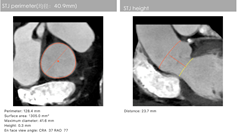

主动脉CT

陈凯明、刘浪教授团队术前总结了该病例特点:此例患者为单纯主动脉瓣返流,升主动脉直径41mm,瓣环周长79.8 mm,流出道周长86.2 mm,左心室扩大明显,特别是主动脉瓣环和瓣叶没有钙化组织, 升主动脉增宽, 喇叭口型左室流出道。这些特殊解剖特点使TAVR支架瓣膜锚定难度大,术中或术后可能出现瓣膜移位等严重并发症。这使得瓣膜的精准定位和释放极为关键。

经过反复评估和研讨后,考虑国内首创的电动可回收输送系统, 以及VitaFlow Liberty™瓣膜的长裙边能提供足够的锚定空间,比较合适类似病例,可以实现快速稳定且较为精准的释放、回收、及瓣膜锚定。最终决定右股动脉入路、植入30型号瓣膜,监护麻醉,经右侧股动脉行TAVR,临时起搏器起搏,植入VitaFlow 30瓣膜。